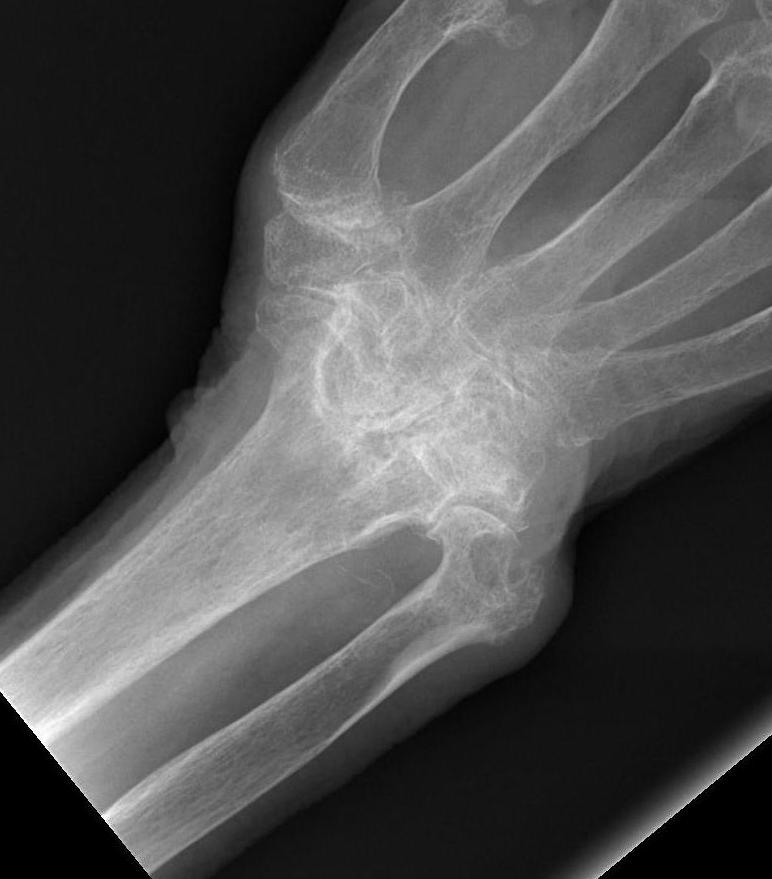

RA wristRA wrist

Xray

Rheumatoid WristRheumatoid Wrist Carpal Collapse